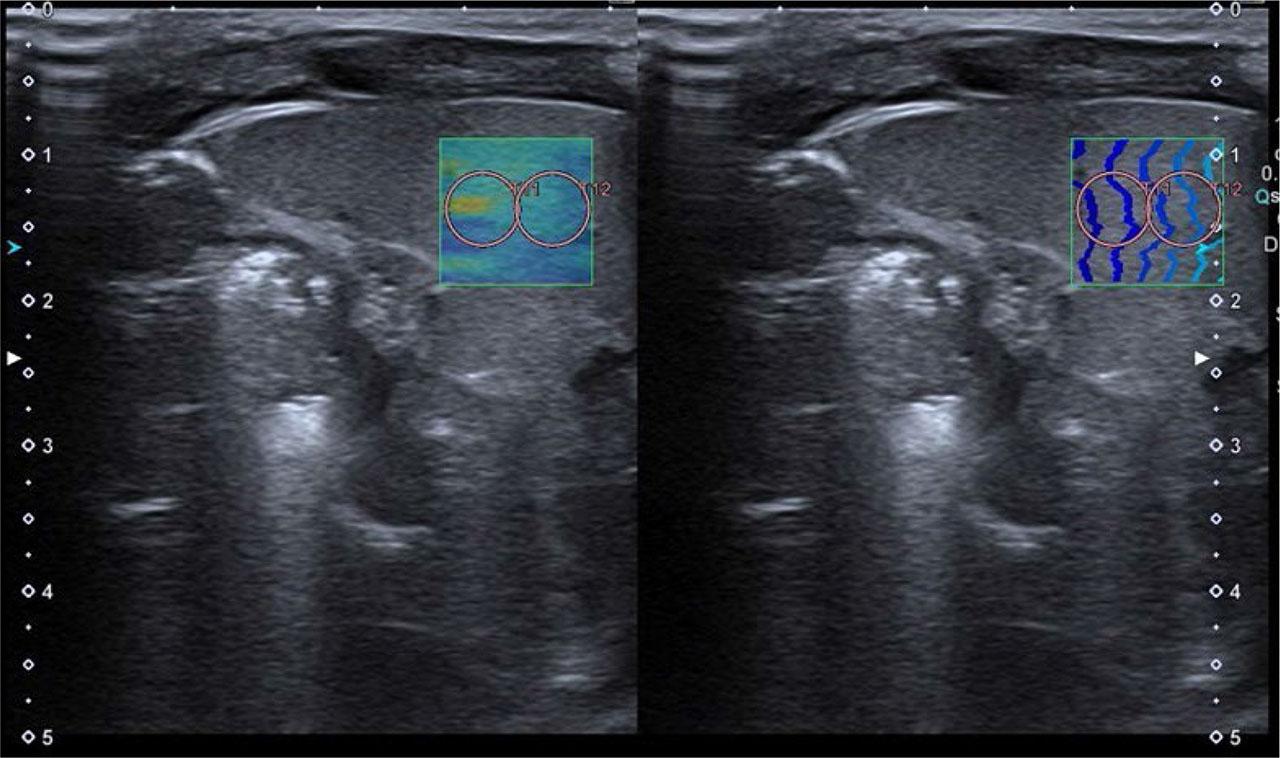

Hepatic, splenic and renal elasticity was measured using the 2D-SWE method during an ultrasound examination (the same device and transducer used for B-mode US), with Canon Aplio i600 system, a14L5 linear transducer (10 MHz), neonatological preset, in spontaneously breathing newborns. A minimum food intake interval of 60 minutes was required. The liver and spleen were assessed with the newborn in the supine position. The right hepatic lobe was assessed under the right costal arch or in the right intercostal space, the left hepatic lobe was assessed in the midline, under the costal arch, achieving optimal transducer placement. The spleen was examined in the left intercostal space or under the left costal arch, achieving optimal transducer placement. The kidneys were assessed in the prone position, from the dorsal side, in the middle part of the kidney, in the view transverse to the long axis. The transducer was placed perpendicularly to the surface of the examined organs, avoiding additional pressure with the transducer. Before taking measurements, a color-coded uniform area of the measurement map (elastogram) was determined using the wave propagation map (option available in the device). The measurements were done below the organ capsule, with the ROI placed within the elastogram so that it was filled with a uniform color, and with wave lines arranged in parallel, equally spaced on the propagation map. The above steps were repeated to obtain a series of 5 measurements (ROI). The ROI size was 5 mm for the right and left lobes of the liver, spleen and kidneys. Examples of 2D-SWE examinations of the right and left lobes of the liver, spleen and kidney are illustrated in Fig. 1, Fig. 2, Fig. 3, Fig. 4. In the kidney examination, the ROI included the renal parenchyma (cortex and pyramid) in such a way that the position of the pyramid (long axis) was parallel to the US beam, excluding the lumens of the calyces and the renal pelvis. The results for each organ were obtained based on the calculation performed by the application installed by the manufacturer in the US device, based on a series of 5 measurements.

An exemplary spleen elasticity measurement, with a color-coded and a wave propagation map, two ROIs are marked

An exemplary right kidney elasticity measurement. ROI covering renal parenchyma (cortex and pyramid), excluding calyceal and renal pelvic lumens